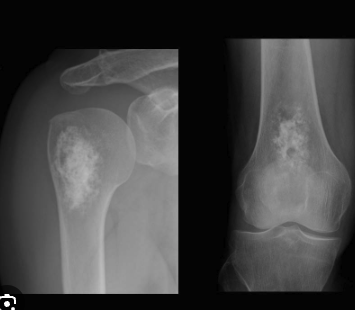

A

Enchondroma

The ARCS AND RINGS is the more classic textbook look with the irregularly speckled calcification of chondroid matrix

Just like fibrous dysplasia, classic matrix is not found in the fingers or toes